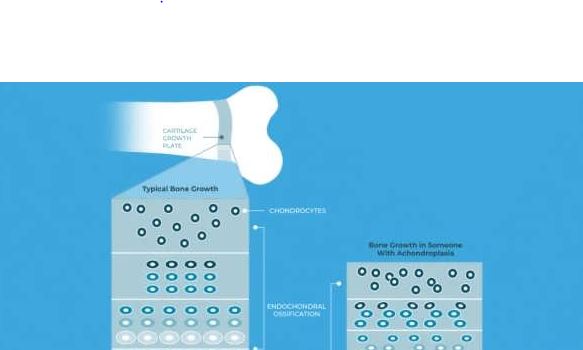

صفحات رشد؛ کارخانه افزایش قد

مهمترین بخش برای رشد قدی ما، ناحیهای جادویی به نام «صفحه رشد» است. این صفحه، یک نوار باریک غضروفی است که بین تنه و سرِ استخوان قرار دارد. در اینجا اتفاقات جالبی میافتد:

تکثیر: سلولهای غضروفی به سرعت تقسیم میشوند.

بزرگ شدن: سلولها حجیم میشوند و طول استخوان را افزایش میدهند.

استخوانی شدن: در نهایت، این سلولهای غضروفی میمیرند و توسط بافت استخوانی جایگزین میشوند.

این روند باعث میشود استخوان از دو طرف کشیده شده و قد فرد بلندتر شود.